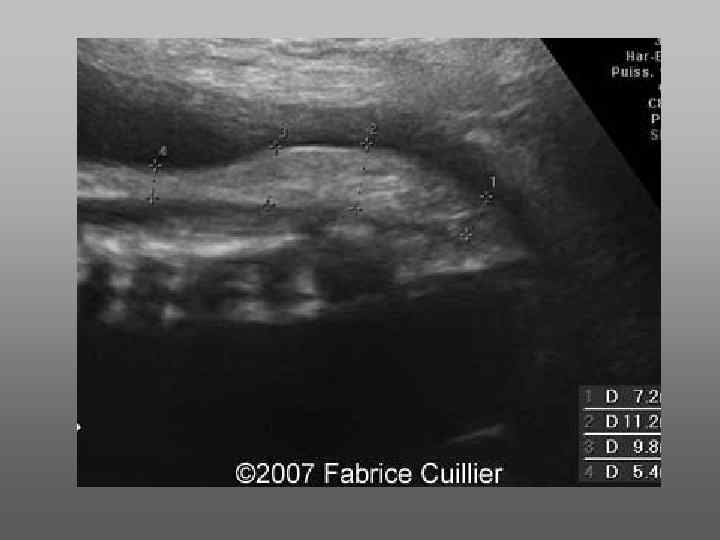

Диагностика • При осмотре позвоночника – осмотр задних центров оссификации. В норме они расположены параллельно другу или под незначительным углом.

При Spina bifida возникает U или Y – образный дефект

Небольшие дефекты чаще диагностируются при тщательном осмотре в поперечной плоскости